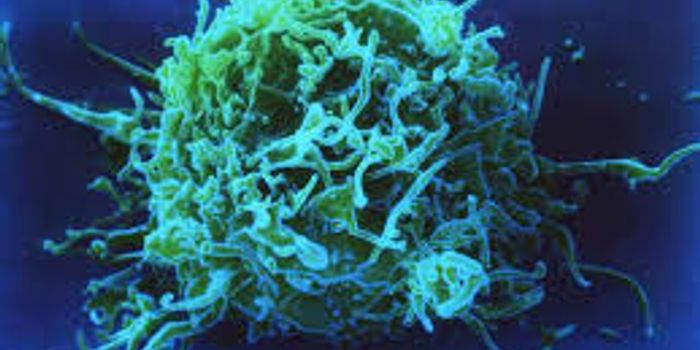

JUN 26, 2015CancerOne reason why cancer is so harmful is that it can trick "checkpoint" proteins found on the immune system's T cells, vir ...